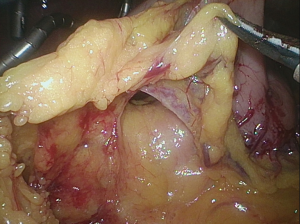

Hiatal dissection

Following completion of the lymphadenectomy, we turn to the hiatal dissection. The hiatus is opened medial to the right crus. The confluence of the crura and left crus are exposed posteriorly (Figure 20). This is facilitated by retracting the resected proximal stomach to the patient’s left. I expose the descending thoracic aorta above the hiatus and skeletonize it, sweeping all the fatty tissue up with the esophagus (Figure 21). I then come around to the right and open into the right pleural space, again taking the fatty tissue superior and adjacent to the hiatus with the esophagus. I continue around anteriorly and skeletonize the posterior pericardium (Figure 22). I divide the right inferior pulmonary ligament close to the pulmonary parenchyma so that the lymph node bearing tissue in the ligament is included with our resected specimen (Figure 23). I retract the resected proximal stomach to the patient’s right and similarly resect the perihiatal fatty tissue, the left pleura and left pulmonary ligament proceeding from posterior to anterior until I join the plane of dissection on the posterior pericardium. The hiatal dissection is facilitated by retracting each crus laterally to aid visualization of the lower mediastinum. We continue the dissection as high as is comfortable. We do not attempt to completely divide the inferior pulmonary ligaments and are careful as we proceed superiorly to avoid injury to the inferior pulmonary veins.